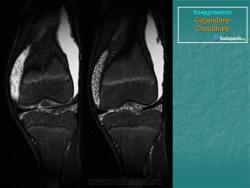

Хондроматоз внутрисуставной (синовиальный)

Приложения:

1.hon_.slayd165.jpg2.hon_.slayd166.jpg3.hon_.slayd167.jpg4.hon_.slayd168.jpg5.hon_.slayd169.jpg